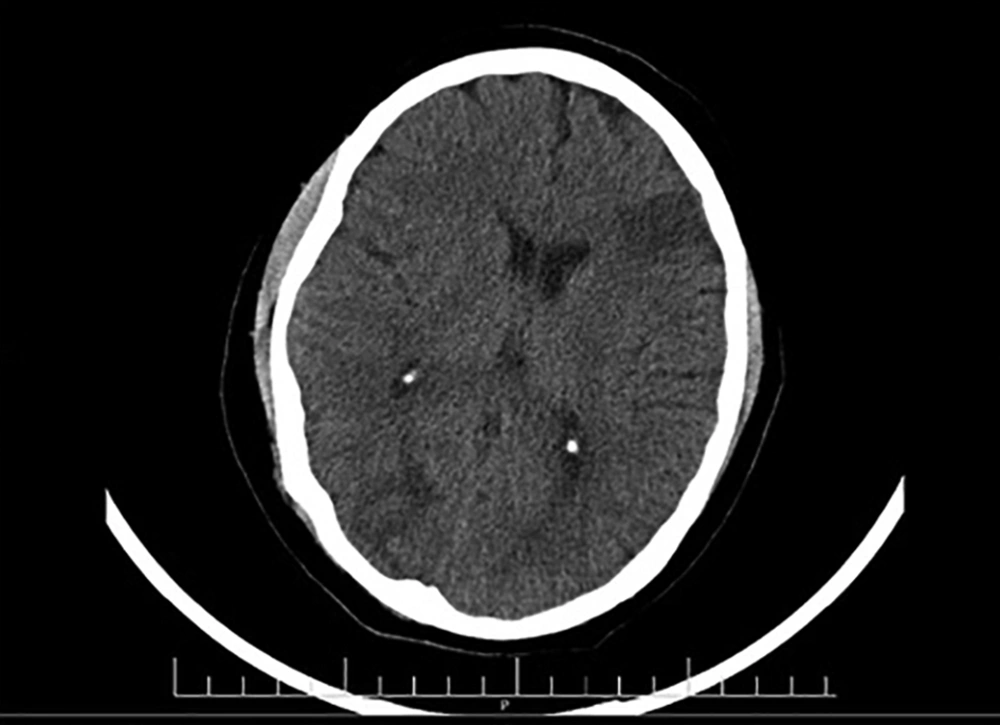

He was examined by an ophthalmologist for blurred vision and subretinal mass, optic disk swelling with hemorrhage and hypopyon, and creamy yellow exudate, as a complication of the retinal abscess, were detected. He was given an antibiotic therapy based on the CT and MRI results and the diagnosis of multiple brain abscesses (Figures 2 and 3). Due to the possibility of toxoplasma following brain and retinal abscesses, the patient received vancomycin, ceftriaxone, metronidazole, and cotrimoxazole, and the improvement of symptoms and normal state of consciousness were observed.

Brain MRI (navigation protocol; with and without GD): MRI shows multifocal vasogenic edema of the bilateral, parietal, right occipital, right temporal, left frontal lobes, and subcortical white matter lesions in both cerebellar hemispheres, indicating a multifocal abscess. No evidence of thrombosis, aneurysm, or AVM was detected in brain MRV and MRA scans.